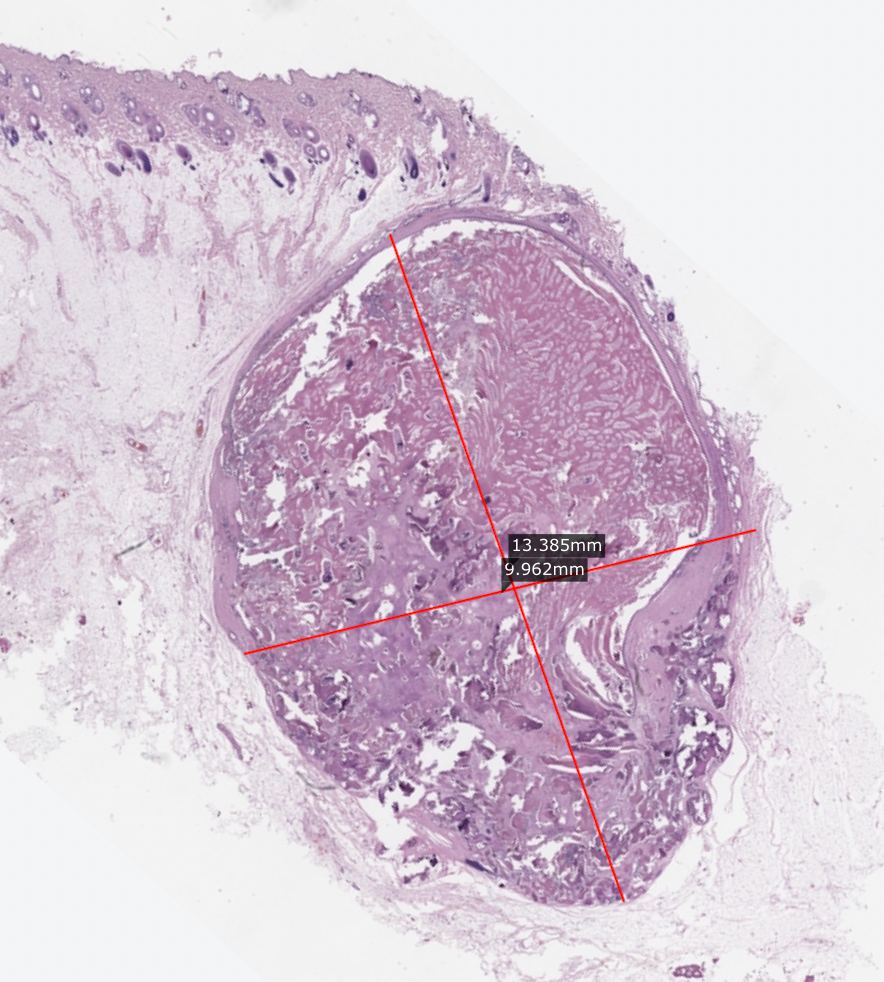

Базально - клеточная опухоль